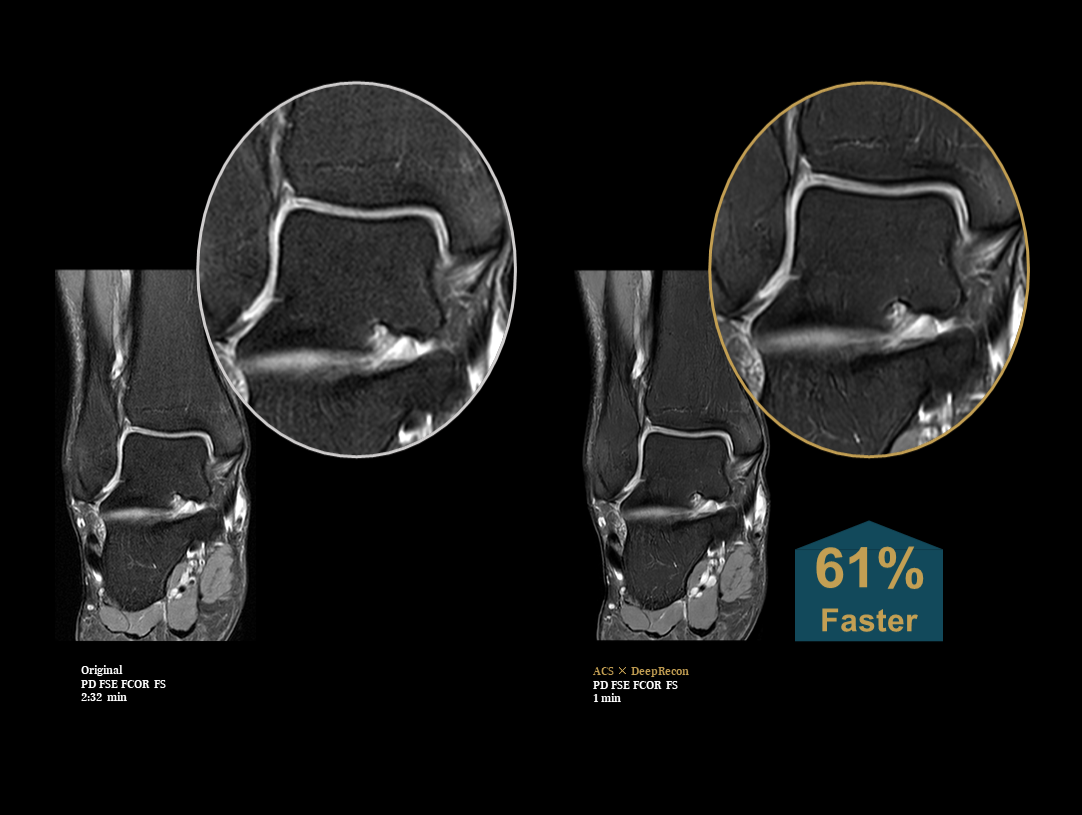

The high performance gradients improves data acquisition and scanning speed, which achieves higher work efficiency.